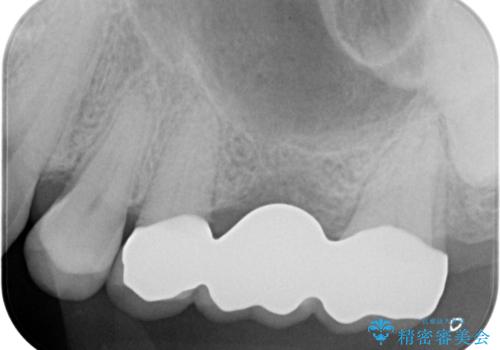

- 左上の奥歯を何とか保存していた患者様です。

今回、残していた歯根から歯茎が大きく腫れ、長期的な予後を期待できないことを考慮し、抜歯してブリッジでの治療を行いました。

ブリッジでの修復は、抜歯後に歯がなくて噛みにくい期間が一切ありません。

歯茎の状態も良く、適合の良いブリッジを装着することができました。